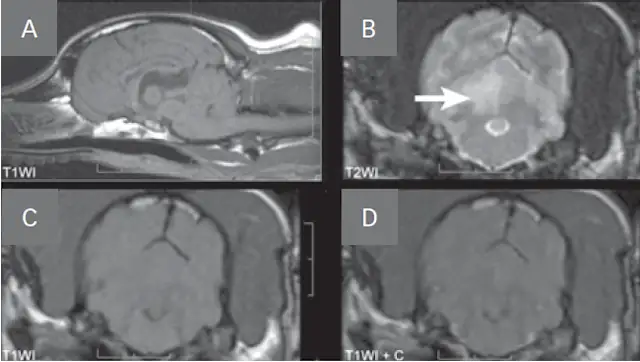

• The classic MRI characteristic of an ischemic stroke (Figure 1, see image gallery below) is an intra-axial lesion (often wedge-shaped) that is hyperintense (bright) on T2-weighted and fluid attenuation inversion recovery (FLAIR) images, iso- to hypointense (dark) on pre-contrast T1-weighted images, and minimal to no contrast enhancement.

FIGURE 1

MRI images of a dog with a right cerebellar infarct (A). Note the wedge-shaped intra-axial lesion in the right dorsal cerebellar gray matter (arrow) that is hyperintense on T2-weighted images (B), isointense on T1-weighted images (C), and does not contrast enhance (D).